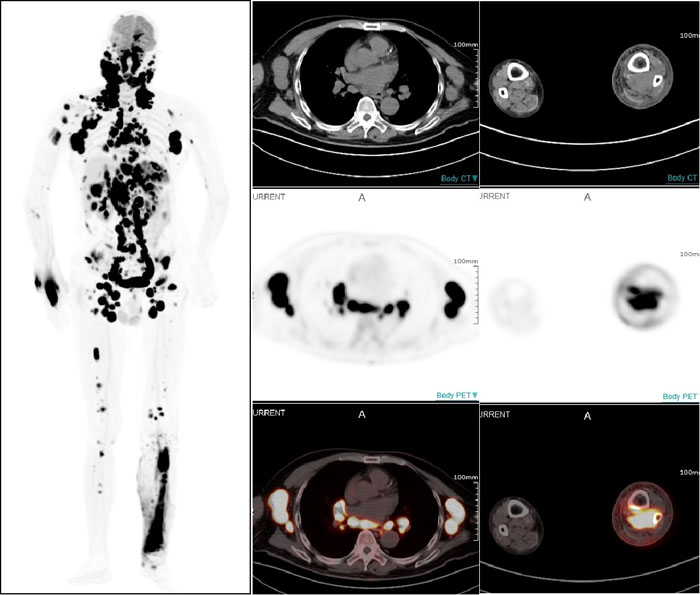

PET/CT显示:全身多部位淋巴结和多个结外器官及不易发现的左小腿后方肌肉组织淋巴瘤受累病灶

一名67岁男性患者因近期无明显诱因出现左颈部淋巴结肿大而就医,淋巴结切检病理诊断为非霍奇金弥漫大B细胞淋巴瘤。借助全景动态Total-body PET/CT扫描,不仅确认了此前的诊断,还发现肿瘤已广泛累及全身多处淋巴结及乳腺、胸膜、肝脏、脾脏、胃等多个结外器官。更令人称奇的是,连平时难以察觉的右小腿深部肌肉组织病变也被准确捕捉。这一全面而精确的影像信息,有效提升了治疗的针对性,为医生制定个性化治疗方案奠定了坚实基础。

设备全身动态采集的性能,清晰展现出药物在体内的流动、扩散及被组织器官摄取并代谢的全过程,帮助医务人员观察药代动力学改变,可以预见,将为肿瘤诊疗、新药研究、细胞追踪等领域带来更多革命性突破。